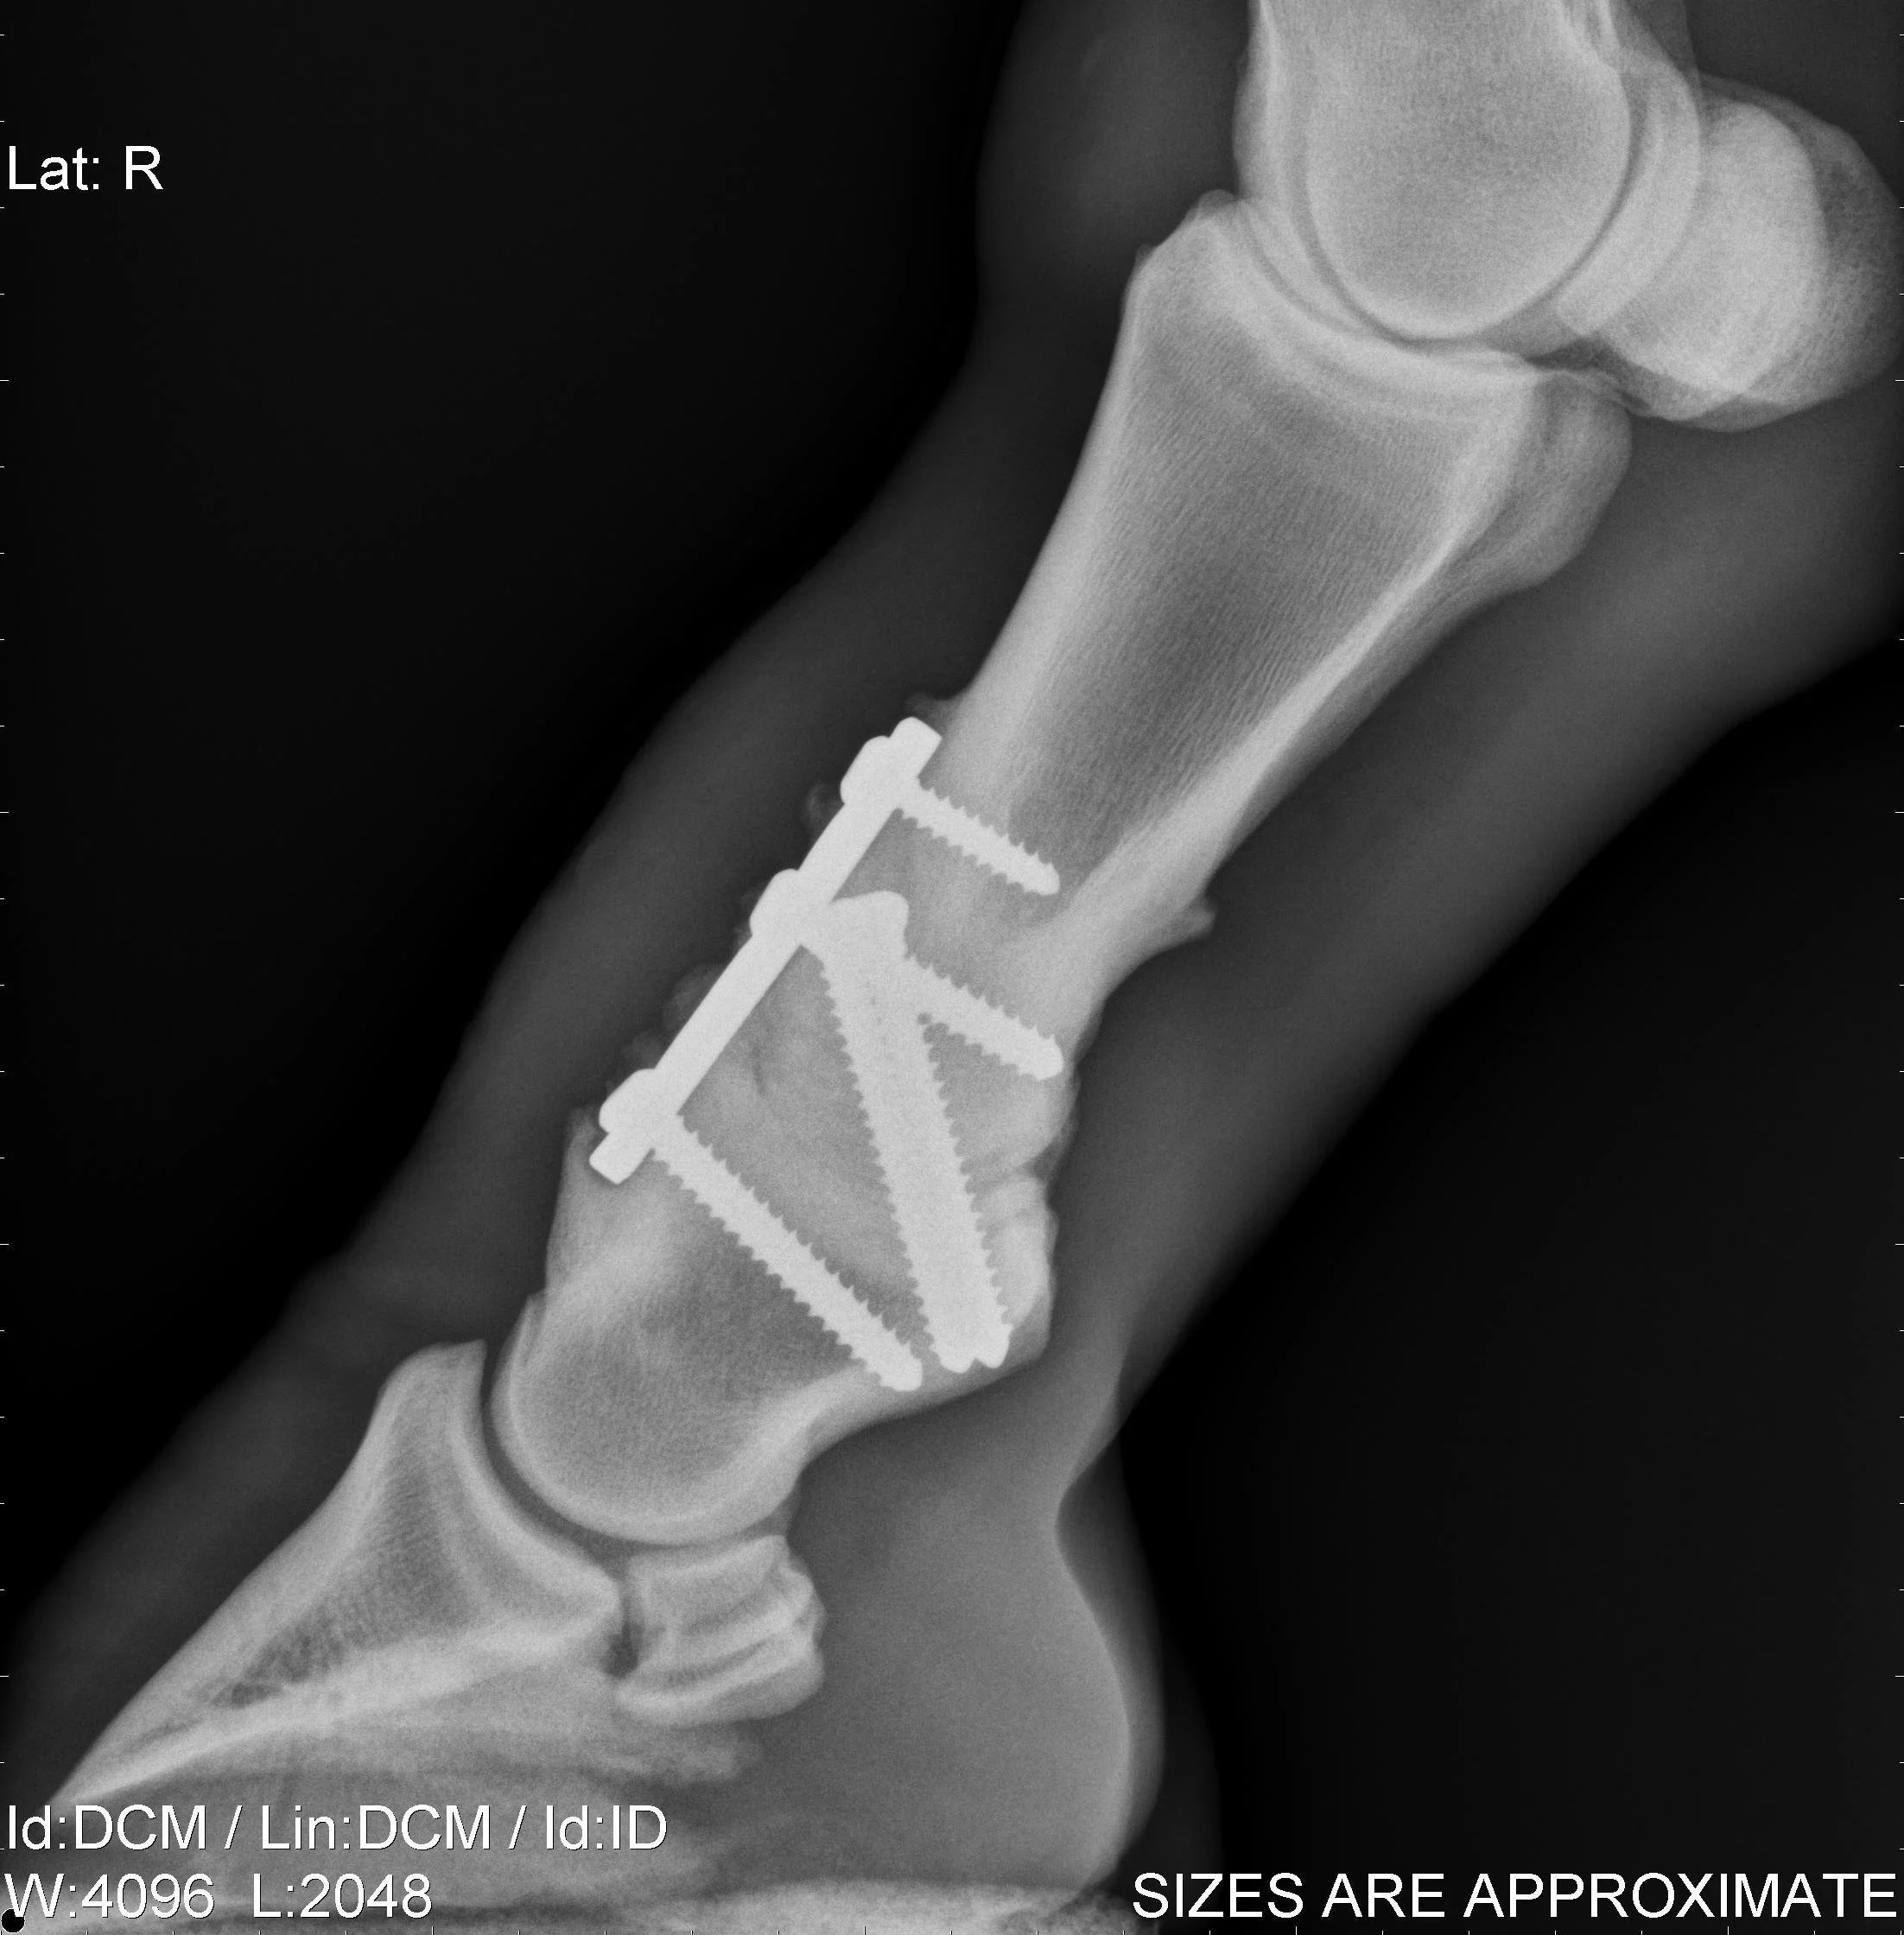

Orthopaedic injuries are commonplace in both racing, competition and pleasure horses. REC Equine Specialist surgeons are highly experienced in the treatment of these conditions using the latest arthroscopic and fracture repair techniques.